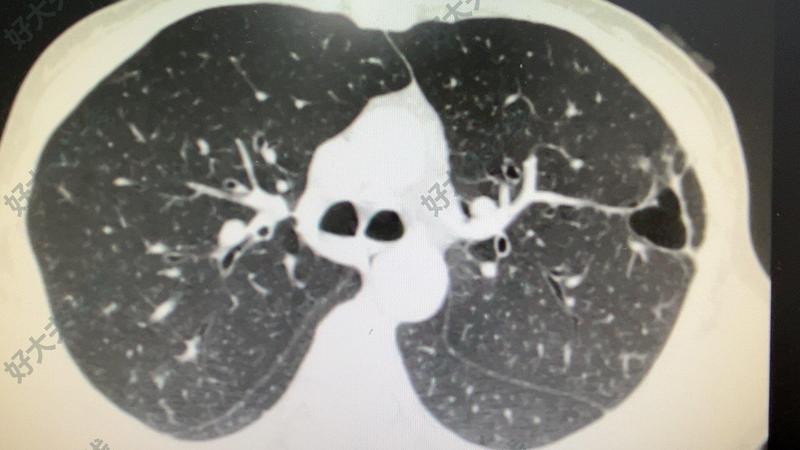

臨床上我們常遇到一些患者,肺部CT提示結(jié)節(jié),在醫(yī)生指導(dǎo)下抗炎后觀察三個(gè)月或半年,再復(fù)查結(jié)節(jié)反而變大了,就以為排除了炎癥,應(yīng)該是肺癌,于是就選擇手術(shù)了,結(jié)果病理是結(jié)核性的。這讓病人白白挨了一刀!主要原因是因?yàn)槲覀兒鲆暳私Y(jié)核感染后出現(xiàn)的肺結(jié)節(jié),結(jié)核結(jié)節(jié)如果沒有有效抗結(jié)治療,單純抗炎肯定沒效果,所以結(jié)節(jié)就發(fā)展變大了呀!???我們醫(yī)院因?yàn)榻?jīng)常接觸肺結(jié)核病人,接觸結(jié)核性結(jié)節(jié)多一些,也接觸了好多術(shù)后病理為結(jié)核的肺結(jié)節(jié)病人,建議對(duì)于肺結(jié)病人一定要問病人有無結(jié)核病人接觸史,有無肺核史,更要注意排查一下是否有結(jié)核感染!以免漏診誤診!讓患者白挨一刀!

ct可以看出來是不是肺結(jié)核嗎?

作者:上海十院中西醫(yī)整合肺結(jié)節(jié)中心申長興副主任醫(yī)師本科普為上海市健康科普專項(xiàng)資助項(xiàng)目:項(xiàng)目編號(hào):JKKPZX-2023-A16肺結(jié)核,乙類傳染病,指結(jié)核病變發(fā)生在肺、氣管、支氣管和胸膜等部位。主要分為原發(fā)性肺結(jié)核、血行播散性肺結(jié)核、繼發(fā)性肺結(jié)核、氣管(支氣管)結(jié)核、結(jié)核性胸膜炎五種類型。肺結(jié)核是我國發(fā)病、死亡人數(shù)最多的重大傳染病之一。目前我國仍是全球30個(gè)結(jié)核病高負(fù)擔(dān)國家之一。癥狀咳嗽、咳痰≥2周,或痰中帶血或咯血為肺結(jié)核可疑癥狀。肺結(jié)核多數(shù)起病緩慢,部分患者可無明顯癥狀,僅在胸部影像學(xué)檢查時(shí)發(fā)現(xiàn)。隨著病變進(jìn)展,可出現(xiàn)咳嗽、咳痰、痰中帶血或咯血等,部分患者可有反復(fù)發(fā)作的上呼吸道感染癥狀。肺結(jié)核還可出現(xiàn)全身癥狀,如盜汗、疲乏、間斷或持續(xù)午后低熱、食欲不振、體重減輕等,女性患者可伴有月經(jīng)失調(diào)或閉經(jīng)。少數(shù)患者起病急驟,有中、高度發(fā)熱,部分伴有不同程度的呼吸困難。病變發(fā)生在胸膜者可有刺激性咳嗽、胸痛和呼吸困難等癥狀。病變發(fā)生在氣管、支氣管者多有刺激性咳嗽,持續(xù)時(shí)間較長,支氣管淋巴瘺形成并破入支氣管內(nèi)或支氣管狹窄者,可出現(xiàn)喘鳴或呼吸困難。少數(shù)患者可伴有結(jié)核性超敏感癥候群,包括:結(jié)節(jié)性紅斑、皰疹性結(jié)膜炎/角膜炎等。兒童肺結(jié)核還可表現(xiàn)發(fā)育遲緩,兒童原發(fā)性肺結(jié)核可因氣管或支氣管旁淋巴結(jié)腫大壓迫氣管或支氣管,或發(fā)生淋巴結(jié)-支氣管瘺,常出現(xiàn)喘息癥狀。當(dāng)合并有肺外結(jié)核病時(shí),可出現(xiàn)相應(yīng)累及臟器的癥狀。體征早期肺部體征不明顯,當(dāng)病變累及范圍較大時(shí),局部叩診呈濁音,聽診可聞及管狀呼吸音,合并感染或合并支氣管擴(kuò)張時(shí),可聞及濕性啰音。病變累及氣管、支氣管,引起局部狹窄時(shí),聽診可聞及固定、局限性的哮鳴音,當(dāng)引起肺不張時(shí),可表現(xiàn)氣管向患側(cè)移位,患側(cè)胸廓塌陷、肋間隙變窄、叩診為濁音或?qū)嵰簟⒙犜\呼吸音減弱或消失。病變累及胸膜時(shí),早期于患側(cè)可聞及胸膜摩擦音,隨著胸腔積液的增加,患側(cè)胸廓飽滿,肋間隙增寬,氣管向健側(cè)移位,叩診呈濁音至實(shí)音,聽診呼吸音減弱至消失。當(dāng)積液減少或消失后,可出現(xiàn)胸膜增厚、粘連,氣管向患側(cè)移位,患側(cè)胸廓可塌陷,肋間隙變窄、呼吸運(yùn)動(dòng)受限,叩診為濁音,聽診呼吸音減弱。原發(fā)性肺結(jié)核可伴有淺表淋巴結(jié)腫大,血行播散性肺結(jié)核可伴肝脾腫大、眼底脈絡(luò)膜結(jié)節(jié),兒童患者可伴皮膚粟粒疹。肺結(jié)節(jié)陳舊病灶和肺結(jié)節(jié)關(guān)系緊密肺結(jié)核自愈或治愈后遺留的陳舊病灶往往表現(xiàn)為肺結(jié)節(jié),而且常分布在結(jié)合好發(fā)位置(兩肺上葉、下葉基底段),需要仔細(xì)鑒別,以免誤診。肺結(jié)核的診斷是以病原學(xué)(包括細(xì)菌學(xué)、分子生物學(xué))檢查為主,結(jié)合流行病史、臨床表現(xiàn)、胸部影像、相關(guān)的輔助檢查及鑒別診斷等,進(jìn)行綜合分析做出診斷。以病原學(xué)、病理學(xué)結(jié)果作為確診依據(jù)。兒童肺結(jié)核的診斷,除痰液病原學(xué)檢查外,還要重視胃液病原學(xué)檢查。預(yù)防1.控制傳染源及時(shí)發(fā)現(xiàn)并治療。2.切斷傳播途徑注意開窗通風(fēng),注意消毒。3.保護(hù)易感人群接種卡介苗,注意鍛煉身體,提高自身抵抗力。

治療前患者肺結(jié)核,抗結(jié)核治療療程近結(jié)束。大部分病灶好轉(zhuǎn)。左上肺2個(gè)小結(jié)節(jié)病灶,無變化?;颊邅砦议T診,CT影像為典型早期腫瘤改變,即收入手術(shù)。治療中考慮患者年輕,2結(jié)節(jié)為磨玻璃結(jié)節(jié),可行肺部分切除且肺結(jié)核殘留空洞與2個(gè)肺結(jié)核位置較近,計(jì)劃術(shù)前結(jié)節(jié)定位后,結(jié)節(jié)連同空洞一并切除。且施行非插管全麻胸腔鏡手術(shù)。即Tubeless。治療后治療后1月患者術(shù)后一月復(fù)查。切口愈合良好。治療后即刻術(shù)后1天復(fù)查胸片,肺復(fù)張良好,采樣淋巴結(jié)?轉(zhuǎn)移。遂拔管出院。然后患者還不敢愿出院,強(qiáng)烈要求住院觀察久一點(diǎn)。